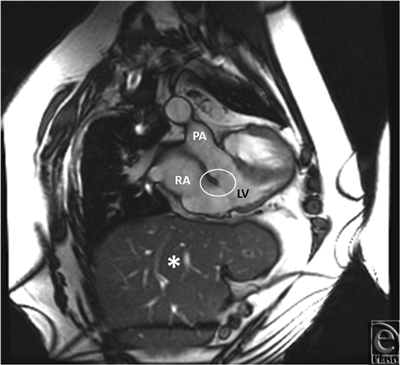

Initial 2D echocardiogram showed severe mitral valve regurgitation with a left ventricular ejection fraction of 35%. Furthermore, the valvular anatomy appeared peculiar; based on right ventricle (RV) and left ventricle morphology, CCTGA was suspected. A transesophageal echocardiography (TEE) was performed for further evaluation. It confirmed our diagnosis of CCTGA. Also, the (TEE) showed a hypertrophied RV and severe systemic AV (SAV) valve regurgitation (Figs 1 and 2). There was no evidence of an atrial septal defect, VSD, or patent ductus arteriosus. An MRI (magnetic resonance imaging) was performed to elucidate the anatomy. It affirmed the diagnosis of CCTGA with a trileaflet SAV that demonstrated severe regurgitation from the systemic ventricle (SV) to left atrium (Figs 3-6). Because of the patient's symptoms and severity of the regurgitation of the SAV, we decided to perform SAV replacement. Preoperative cardiac catheterization showed left dominant coronary circulation with left circumflex and a ramus intermedius originating from left cusp through separate ostia (Figs 7 and 8). Left anterior descending artery originated from proximal right coronary artery through a single ostium from right coronary cusp (Figs 8 and 9). No obstructive coronary heart disease was found and the patient proceeded to surgery.

![]() |